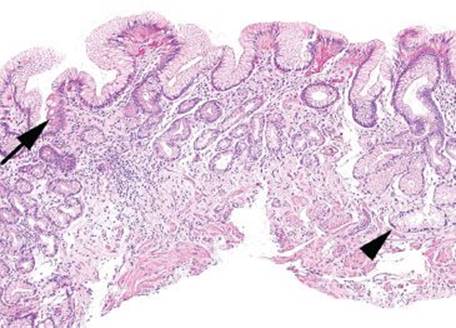

The two most common types of metaplasia seen in the stomach include intestinal metaplasia (IM) and pyloric metaplasia (Figs. 2.106–2.109). Both are the result of chronic gastritis, and consequently both are more frequently encountered in elderly individuals. A third, less common form of metaplasia is pancreatic metaplasia (Figs. 2.110–2.113).

Figure 2.106 Chronic gastritis pattern, intestinal metaplasia, complete, with villiform change, AMAG. This biopsy was removed from the gastric body of a patient with well-developed AMAG. The intestinal metaplasia includes intensely pink Paneth cells at the bases of the pits (arrowhead), indicating complete intestinal metaplasia. Further evidence of advanced intestinal metaplasia can be seen in the villiform architecture of the pits and glands.

Figure 2.107 Chronic gastritis pattern, intestinal and pyloric metaplasia, AMAG. This biopsy from the gastric body shows both intestinal metaplasia (arrow) and pyloric metaplasia (arrowhead). In the setting of total oxyntic atrophy, such as this, a gastrin stain can confirm that this tissue as body/fundus in origin.

Figure 2.108 Chronic gastritis pattern, intestinal and pyloric metaplasia, AMAG (gastrin immunostain). This negative gastrin immunostain from the previous case (Fig. 2.107) verifies the absence of G cells and confirms gastric body/fundus origin, further substantiating an interpretation of AMAG.

Figure 2.109 Chronic gastritis pattern, linear and nodular enterochromaffin cell (ECL) cell hyperplasia, AMAG (chromogranin immunostain). This chromogranin immunostain of the previous figure highlights both linear (arrowhead) and nodular (arrow) ECL cell hyperplasia. The finding of either linear or nodular ECL cell hyperplasia confirms the diagnosis of AMAG.

Figure 2.110 Chronic gastritis pattern, pancreatic metaplasia/heterotopia. Pancreatic differentiation (arrowhead) is seen as a lobule of pancreatic acinar cells and is etiologically nonspecific. The background in this example is unremarkable oxyntic mucosa. In normal stomachs, this finding is probably heterotopic rather than metaplastic whereas in stomachs with autoimmune gastritis, pancreatic type tissue is probably metaplasic.

Pyloric metaplasia is the replacement of the oxyntic mucosa with pyloric glands. Although this finding is highly characteristic of AMAG, it is not always a dominant pattern of injury. More often, adjoining intestinal metaplasia (IM) is far more prominent, particularly at low power. With IM, the cells of the surface and pit epithelium change such that they morphologically and histochemically resemble the small or large bowel, a finding that can be categorized as complete (type I) or incomplete (type II). Complete IM resembles normal small bowel epithelium with fully developed goblet cells, enterocytes with a brush border, and Paneth cells. In advanced cases, the contour of the mucosa develops villiform architecture and crypts. In contrast, incomplete IM (type II) has a mixture of goblet cells and normal gastric epithelium, and it lacks a brush border, Paneth cells, and absorptive cells. IM (complete or incomplete) may be seen in both AMAG and EMAG. Finally, the less common pancreatic acinar metaplasia is found in over 20% of AMAG cases and is frequently seen in conjunction with pyloric or intestinal metaplasia. These nested or lobulated collections of pancreatic acinar cells stain with amylase (75%).

Compartment, Metaplasia Subpattern

In AMAG, IM is a prominent finding in the gastric body/fundus in combination with oxyntic gland atrophy, pyloric metaplasia, and pancreatic metaplasia. By comparison, in EMAG, IM is a prominent finding in the gastric antrum and does not extend to the body/fundus until late in the disease. When IM is limited to the antral mucosa, diagnostic considerations include EMAG (Helicobacter, bile reflux, nonsteroidal anti-inflammatory medication injury, and other direct mucosal toxins [i.e., smoking, alcohol]). Inspection for other concomitant patterns or subpatterns of injury may help suggest the etiology; for example, the presence of antral-based IM with acute gastritis is likely Helicobacter, whereas antral-based IM with reactive/chemical gastropathy is more likely related to bile reflux or other chemical agents.